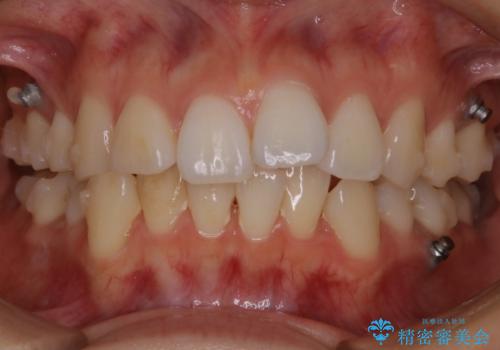

- マウスピース(インビザライン)

- 1年6ヶ月

- 10-30回

- 税込 ¥968,000- (インビザライン コンプリヘンシブパッケージ + マイクロインプラント費用)費用は治療当時の料金となります